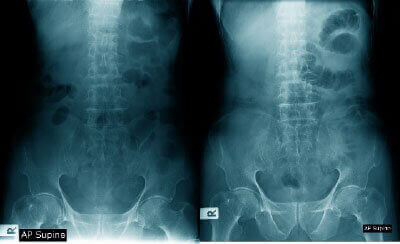

- レントゲンやMRIではどんな問題があるのか?

- 本当の痛みの原因は何なのか?

- 原因を100%改善できる技術を生み出せないか?

など…病院に来る名だたる名医たちと研究した結果…どんな症状や重症の方が来ても、法則性に当てはめれば素人でもゴッドハンドでも、どこにアプローチすればよいか一目で分かるプロセスを作り上げたのです。